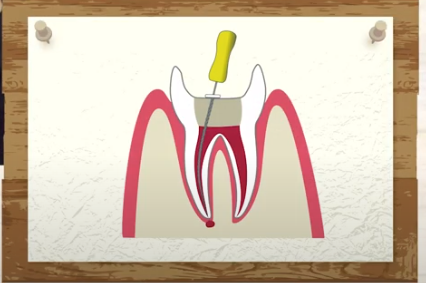

歯の頭があって

歯の根っこがあって

断面で見ますと

骨の中に

根っこが植わっていて

そこに神経、血管があるということです。

神経の治療をするにあたっては

歯の頭の部分が邪魔になるのです。

なので

歯の頭を削ってスパンと落すんです。

そして管のようなトンネルのような神経、血管の入り口が

見えてきます。

ここから針みたいなものを入れて

中を掃除された記憶

あるのではないでしょうか?

断面で見ると

中が綺麗になりますので

その後です

被せものをしようとするのですけれど

安定しませんね

ですので

今度は

杭のようなものを作り

この杭を穴の中に差し込みます。

そうしますと

この杭の頭の部分が

上に出てきますので

これを土台にして

帽子をかぶせる

という治療が多く見受けられます。